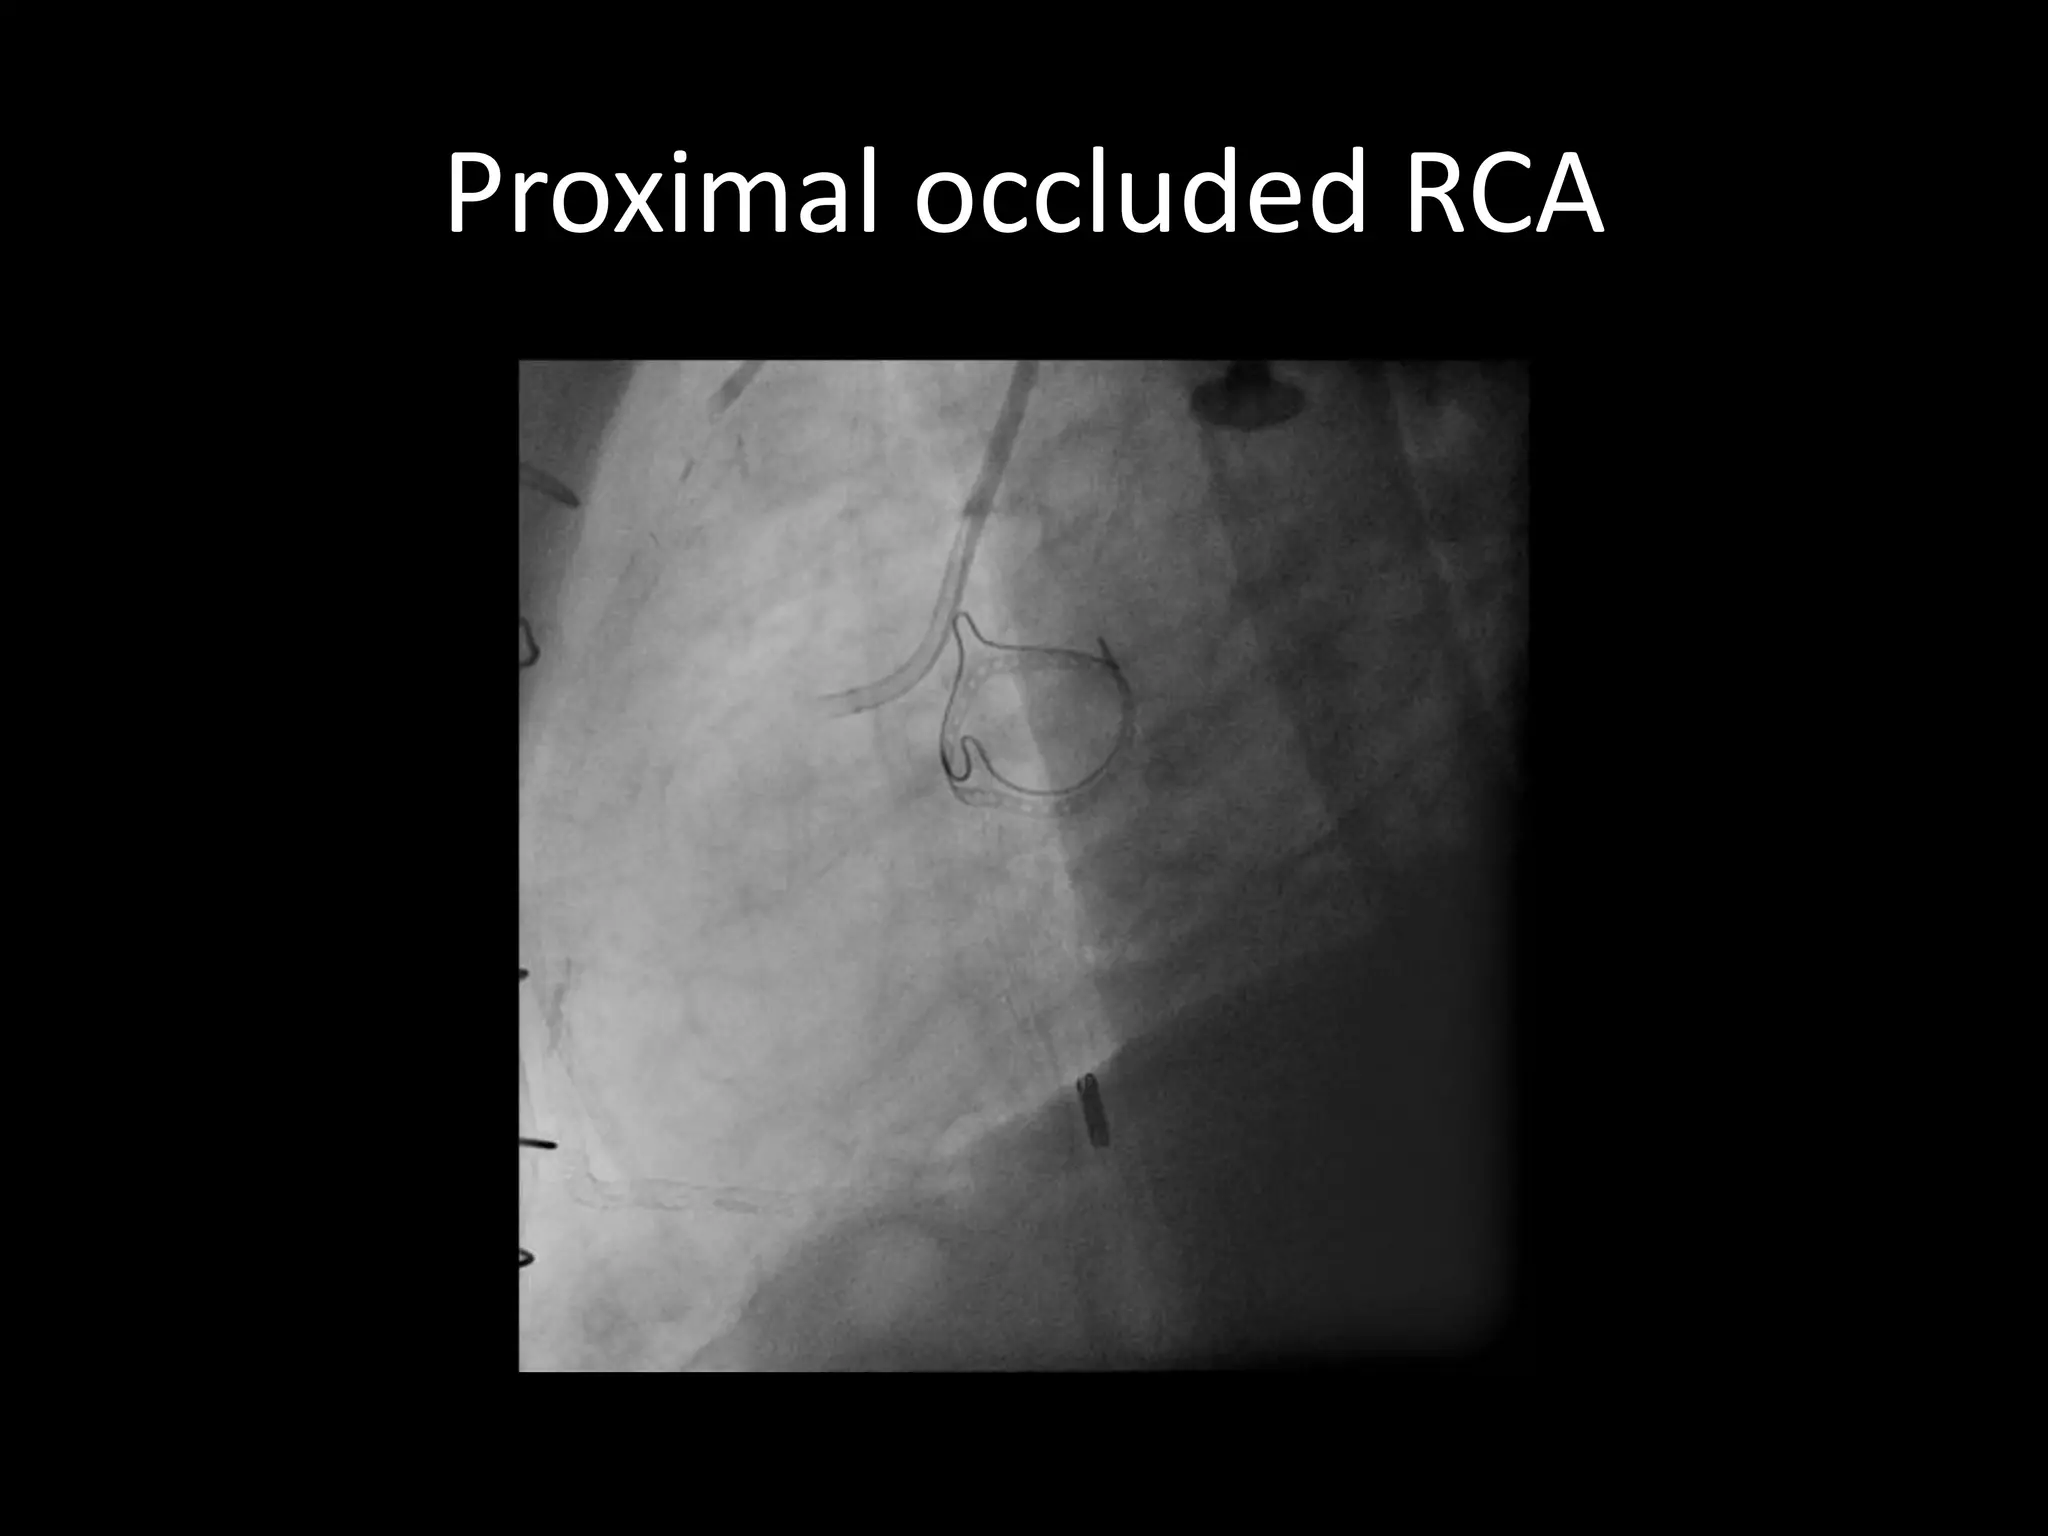

This document provides guidance on evaluating the feasibility of percutaneous coronary intervention (PCI) for a chronic total occlusion (CTO). Key factors to consider include: the patient's tolerance for a long procedure, contrast load, and radiation exposure; the CTO's proximal cap ambiguity, length, distal landing zone, and presence of interventional collaterals; and ensuring good quality angiography. With adequate planning and use of appropriate CTO techniques, feasibility is nearly always present for symptomatic patients. Success rates of CTO-PCI are reported to be 94% when using a planned approach.